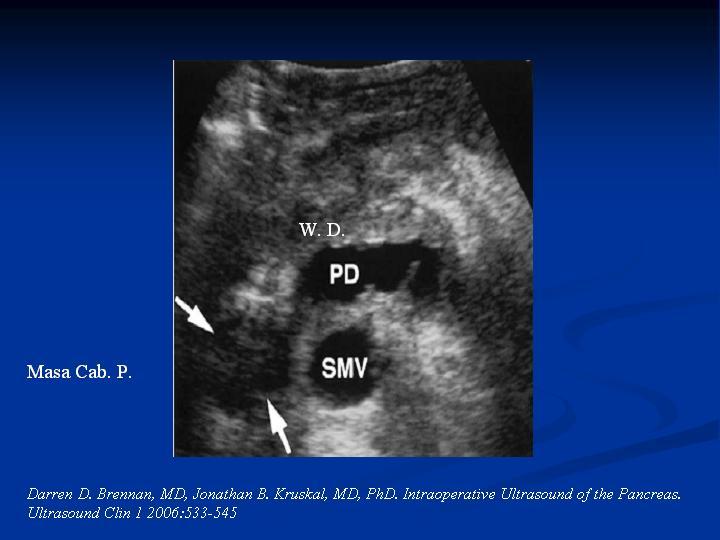

Imagenología en Tumores de Páncreas

Hepatobiliopancreático

| Autor: Andrés Martínez Serrano